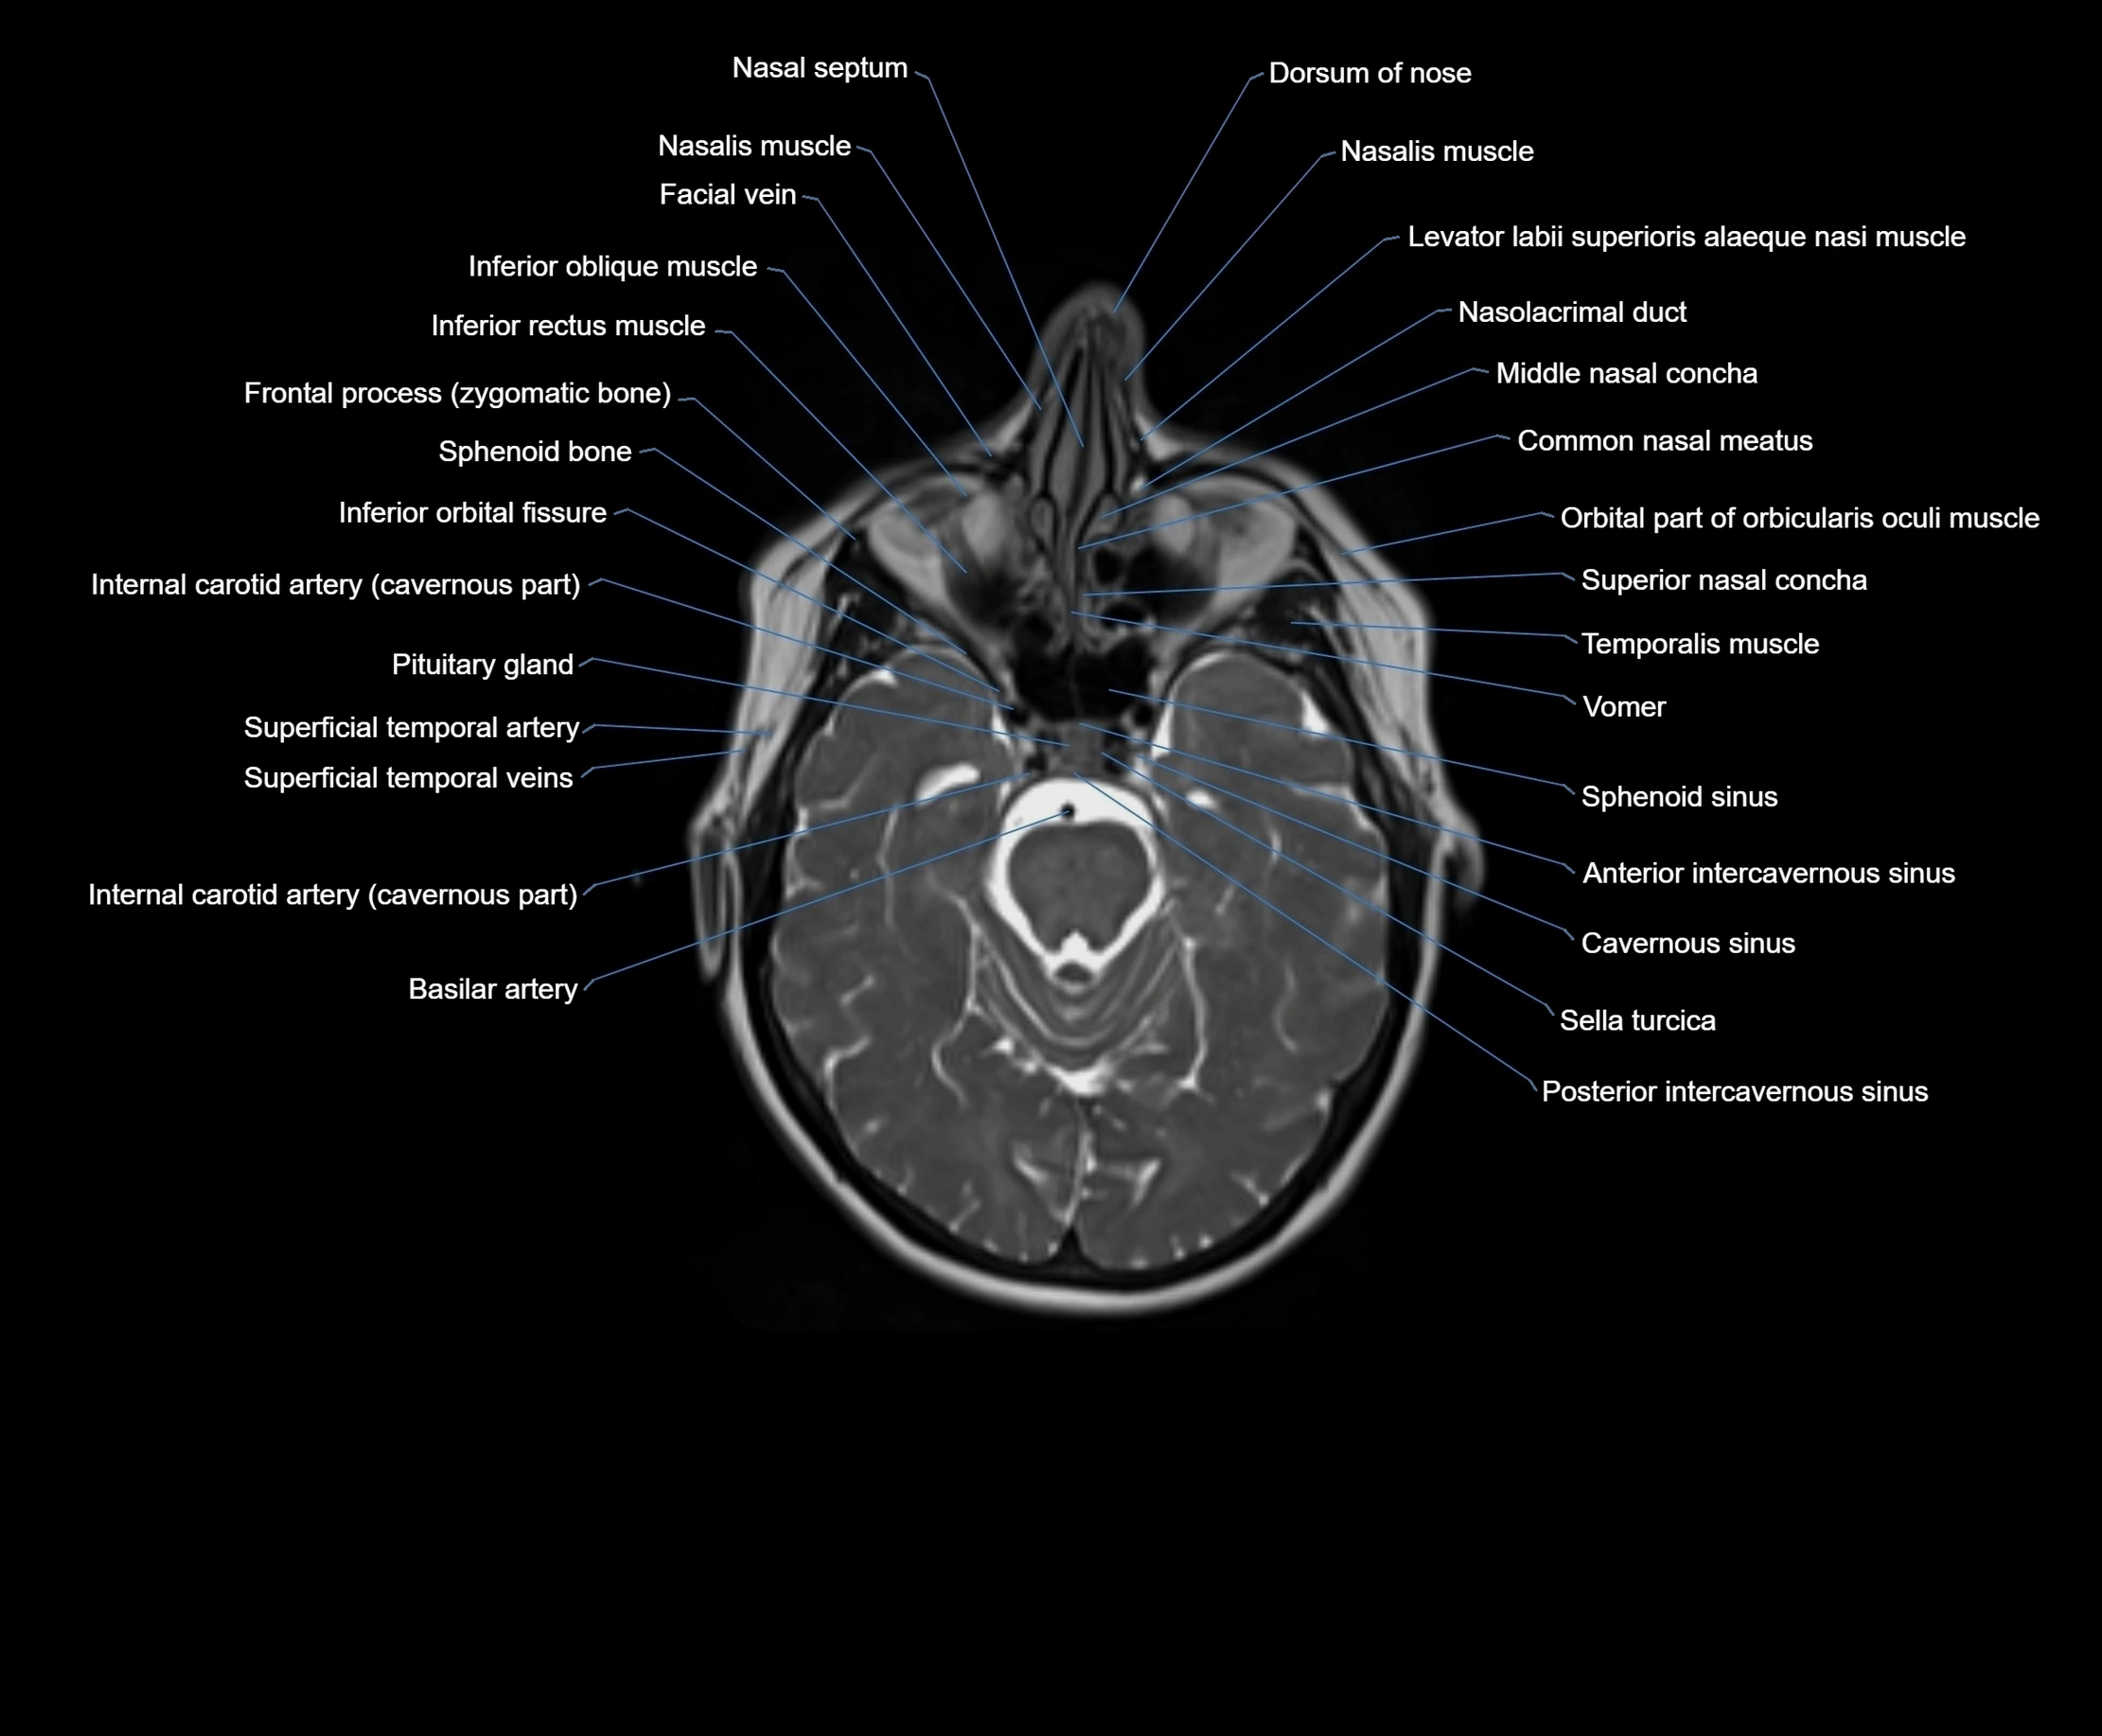

MRI images